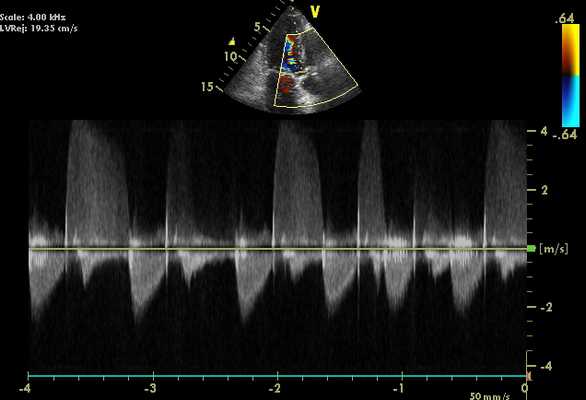

ЭхоКГ с допплерографией при аортальной регургитации

Это полезный метод как для обнаружения AН, так и для оценки ее серьезности. Отображение цветового потока очень показательно, при этом струю AН можно увидеть при попадании в полость ЛЖ на нескольких изображениях, таких как парастернальная длинная ось и апикальная 5-камерная. Импульсный допплер может использоваться в апикальной 5-камерной проекции с выставлением контрольного объема непосредственно проксимальнее аортального клапана. Аортальная недостаточность может быть обнаружен как сигнал выше базовой линии (по направлению к датчику), но поскольку скорость AР обычно высока (> 2 м/с), будет происходить наложение спектров. В этом случае полезен непрерывный волновой допплер, и сигнал будет виден выше базовой линии.

- Струя аортальной регургитации бывает быть трудно отличить от высокоскоростной струи митрального стеноза, особенно в апикальной 5-камерной проекции (2 потока часто сосуществуют!). Цветное допплеровское картирование может подтвердить, какие есть изменения или если оба условия присутствуют, то импульсный допплер используется для отдельного картирования областей ВТЛЖ и MК. Непрерывный допплер при аортальной регургитации показывает сигнал скорости, начинающийся на ранней стадии и продолжающийся в течение диастолы с высокой пиковой скоростью (> 2 м/с). Митральный стеноз выдает сигнал средней диастолической скорости, обычно с максимальной скоростью

Используя импульсно-волновой допплерографию, контрольный объем можно разместить в различных положениях внутри полости ЛЖ, чтобы дать полуколичественное представление о степени тяжести, наблюдая, как далеко в полость ЛЖ проникает струя AР. В целом, легкая АН остается в области АК, умеренная АН остается между выходным трактом левого желудочка (ВТЛЖ) и уровнем МК выше уровня папиллярных мышц, а тяжелая АН распространяется до верхушки ЛЖ. Это дает только грубое и приближенное представление о тяжести регургитации, так как например узкая струя легкой АН может распространяться глубоко в полость ЛЖ, в то время как сильная широкая струя АН может иметь эксцентрический угол и не распространяться далеко в ЛЖ. Используя цветовое отображение потока, ширина струи регургитации непосредственно под AК указывает на серьезность. Это относится к области плохого закрытия клапанов (регургитирующего отверстия). Ширина струи> 60% ширины аорты на уровне створки обычно серьезна. Можно сделать стоп-кадр AР и использовать планиметрию для оценки площади поперечного сечения струи. Длина струи АН в полость ЛЖ на апикальной 5-камерной проекции также может указывать на тяжесть (более длинная струя - более тяжелая АН).

При непрерывном волновом доплеровском режиме наклон скорости замедления доплеровского сигнала AР может дать указание на серьезность, как и интенсивность сигнала (более интенсивный сигнал отражает более серьезную регургитацию на аорте). Основание для этого описано в главе 3. Ретроградный диастолический кровоток в дуге аорты также предполагает тяжелую АН.